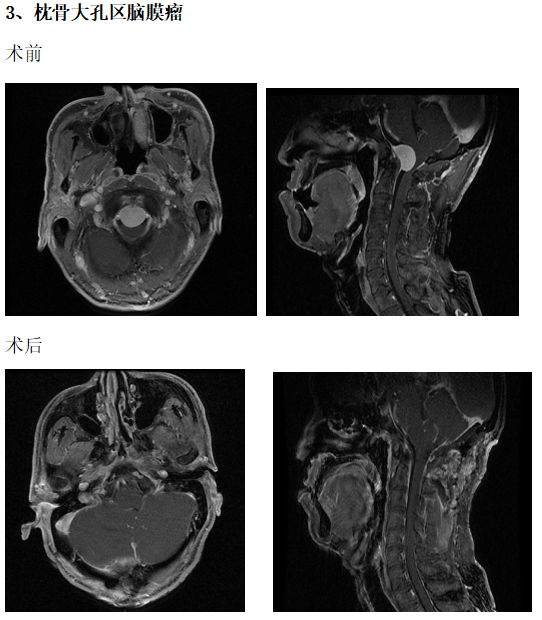

典型病例介绍